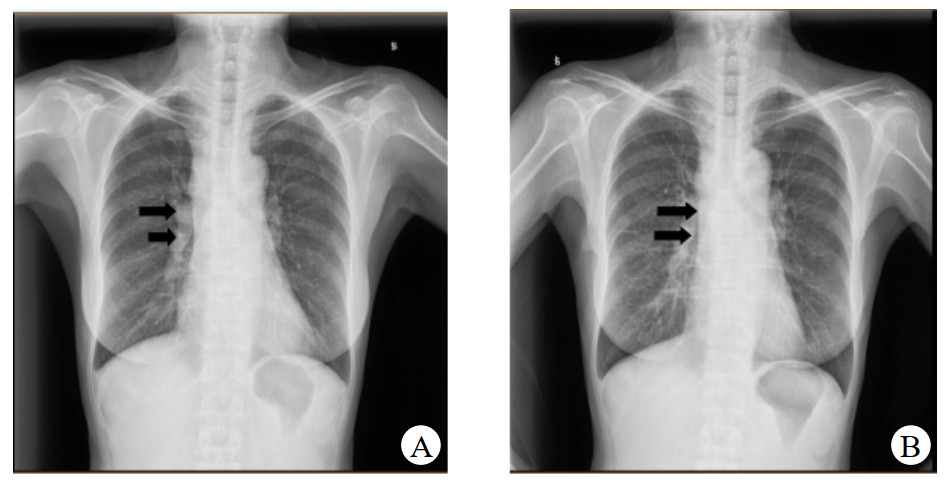

患者于2019-06-17因发热及头痛等不适来本院诊治。查体:体温38.5℃, 心率96次/min,呼吸20次/min,血压132/92 mmHg(1 mmHg=0.133 kPa)。结合症状及既往就诊经历,诊断考虑:发热查因;肺门淋巴结肿大。鉴别诊断:肺结核、淋巴瘤、结节病。同时患者外周血白细胞(WBC)及降钙素原(PCT)升高,不排除细菌感染, 予莫西沙星400 mg治疗5 d, 并在应用抗生素前留取病原学标本。期间行经气管镜超声引导针吸活检术(endobronchial ultrasound-guided transbronchial needlle aspiration, EBUS-TBNA),但无阳性结果。入院后所行的PET-CT提示肿大淋巴结考虑淋巴瘤。双肺小结节,考虑炎性肉芽肿。骨穿无异常结果, 以“肉芽肿(纵膈淋巴结)”为主要诊断出院。图 1为入院后两次胸部平片影像检查结果,可见右肺门影增浓。

| A:2019-07-15检查;B:2019-08-27检查 图 1 CT检查示右肺门影改变 |